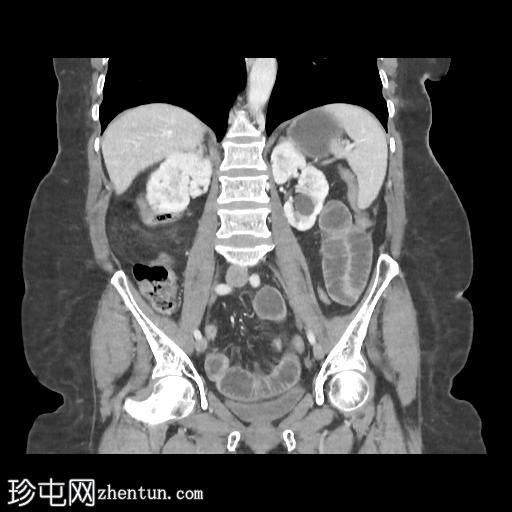

冠状位增强扫描(门静脉期)

4.jpg

胆囊缩小,囊壁增厚,提示慢性炎症改变。胆囊(底部)与十二指肠(球部)腔之间可见细小瘘管,胆囊内及肝内、肝外胆管内均可见气体(胆道积气)。

远端空肠内嵌顿一枚较大的胆结石(3.5 cm),近端空肠袢扩张,回肠袢、末端回肠及结肠均塌陷。

本病例符合典型的里格勒三联征:

异位胆结石

小肠梗阻

胆道积气